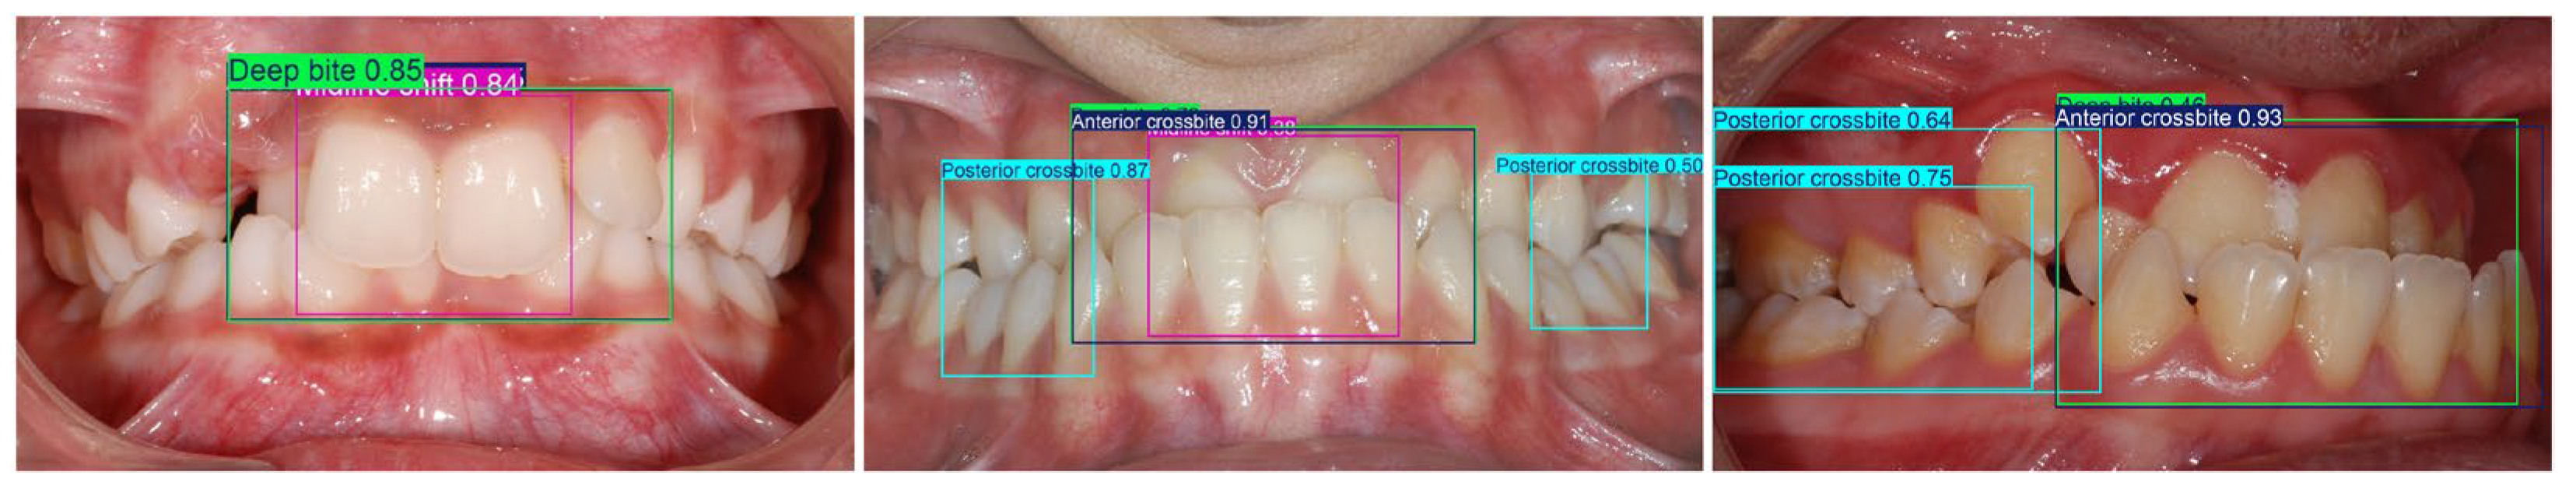

| Big overjet, Anterior crossbite, Deep bite, Head bite, Anterior open bite | BB over the four upper incisors as well as the overlapping lower canines and incisors |

| Anterior crossbite | One or more maxillary incisors occlude lingual/palatal to the mandibular incisors |

| Deep bite | Mandibular incisors are covered too much by maxillary incisors (>50% coverage) |

| Midline shift | The upper and lower dental midlines do not coincide (visible mismatch between the contact points of the central incisors) |

| Posterior crossbite | One or more posterior teeth occlude in reverse transverse relationship: maxillary posterior teeth are positioned lingual/palatal to mandibular posterior teeth |